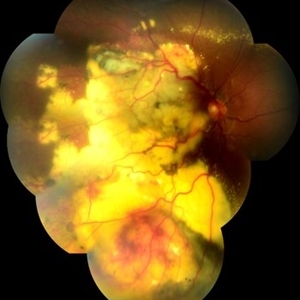

Syphilis Neuroretinopathy

Female patient, 21-years-old, with complaint of low vision in the right eye for 3 years. According to information from the patient's history, at the time she noticed the low vision, it also coincided with a picture of a strong urinary infection as well as episodes of constant tonsillitis. Yes, the patient did not seek medical attention and self-medicated with antibiotics. In ophthalmologic evaluation, as well as examinations of color retinography and ocular fundus autofluorescence, important pigmentary alterations were observed following vascular arches with pigment mobilization in osteoclasts (aspect of a unilateral pigmentary retinitis secondary to the inflammatory process). Which suggested inflammatory process sequelae. Through the laboratory tests, he had positive (+) confirmation for SYPHILIS NEURORETINOPATHY .

Photographer: JEFFERSON R SOUSA - Study Center and Ophthalmological Research Dr. Andre M V Gomes, Institute Dr. Suel Abujamra São Paulo-Brazil

Imaging device: Fundus camera Topcon TRC-50 DX, Imaginet 5.0, angle de 50 graus. Flash 100 / Mosaic with 10 images.

Condition/keywords: autofluorescence imaging, neurosyphilitic optic atrophy, retinitis pigmentosa, syphilis, syphilis neuroretinopathy